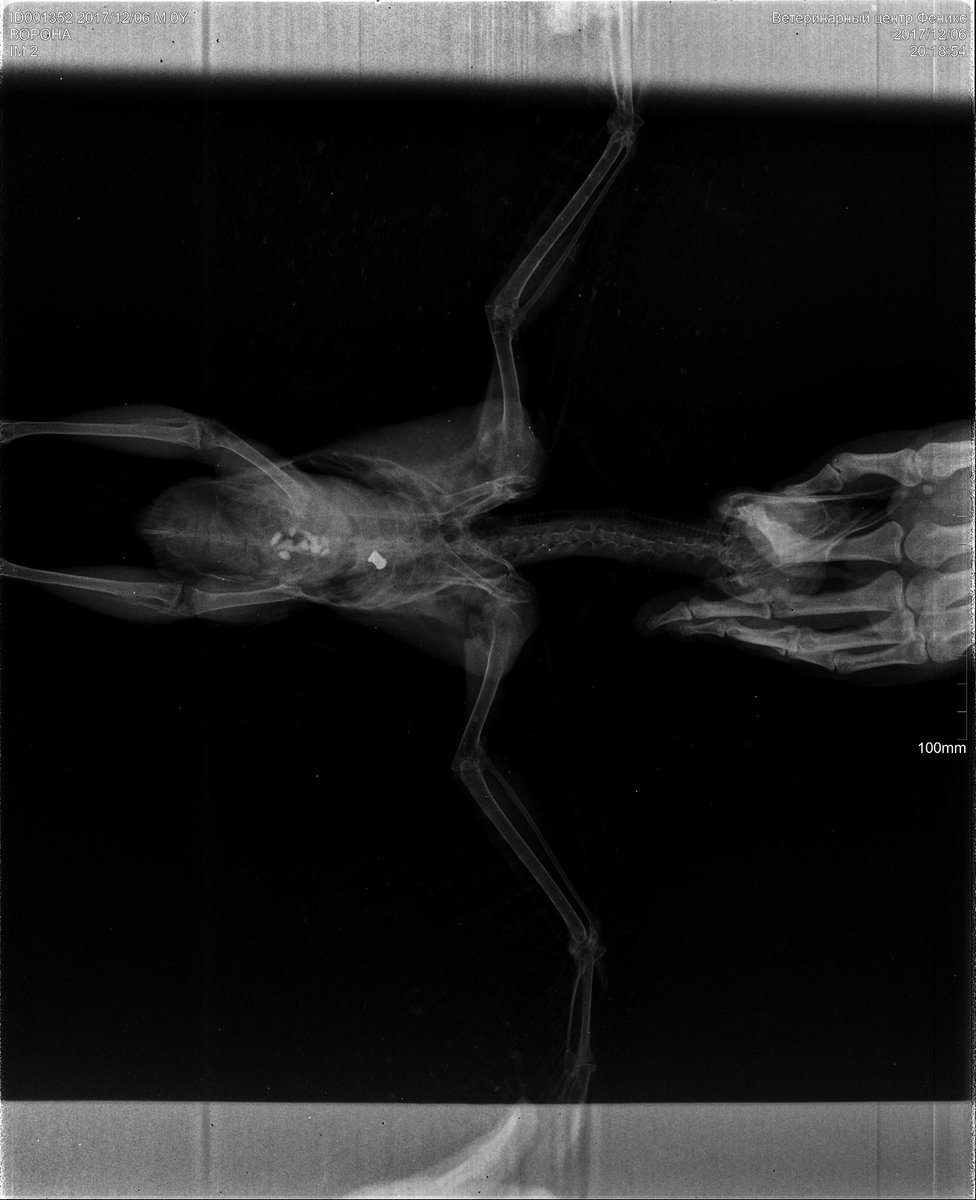

Vikfor Опубликовано 6 декабря, 2017 Автор #3 Опубликовано 6 декабря, 2017 Только попала домой, в итоге с момента того как забрала ворону с ТТК прошло 10 часов! Пришлось ехать в Мск обл, орнитолога смогла найти только там. Это Колотов Владимир. Нашла его по отзывам.Оказалось, что ворону кто-то подстрелил, она, вероятно, упала с ветки, расправила крылья и летела пока были силы, потом, видимо, они закончились и она упала прям на дорогу ТТК. Завтра под общим наркозом ей сделают операцию, чтоб достать пулю, она не задела сам позвоночник и орнитолог сказал, что ворона должна восстановиться. Собираю с миру по нитке на её лечение, общая сумма 8тыс(6тыс операция+стационар, 1тыс осмотр и 1тыс рентген). 4тыс я уже собрала, осталось ещё столько же. Буду очень благодарна любой сумме, контакты карты могу выслать в личном сообщении или можно пересечься где-нибудь в Москве. Буду отписываться по мере наполнения.

Vikfor Опубликовано 7 декабря, 2017 Автор #4 Опубликовано 7 декабря, 2017 К сожалению, ворона умерла сегодня во время операции, пуля задела позвоночный столб и при извлечении повредила позвоночник, что и привело к остановке сердца.К сожалению "кроухантер" (слово, которое я узнала только вчера) не оставил вороне шансов. Очень жаль.Спасибо всем большое за поддержку и желание помочь! Это очень ценно и важно! Огромное всем спасибо!